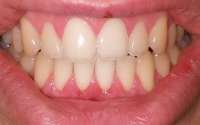

14730060113960.jpg (1696Кб, 3584x2016)

14730060114311.jpg (1712Кб, 3584x2016)

14730060114662.jpg (1558Кб, 3584x2016)

Мои зубки. Запломбировал все дырки коих было много, но внешний вид всё равно оставлял желать лучшего, на последнем приёме у стоматолога спросил насчет отбеливания зубов, какие есть варианты и т.д. она мне ответила, что у меня и так фиговая эмаль и мне нельзя делать отбеливание, дальнейшие расспросы особых результатов не дали. Собственно вопрос - и вправду нет адекватного способа отбелить зубы без вреда для самих зубов? Не очень то хочется бегать желторотиком всю жизнь. И какие еще могут быть способы привести зубы в более привлекательный вид?

>>513114

На чистке зубов был? Что то у тебя между зубов какие то отложения. Или это еда?